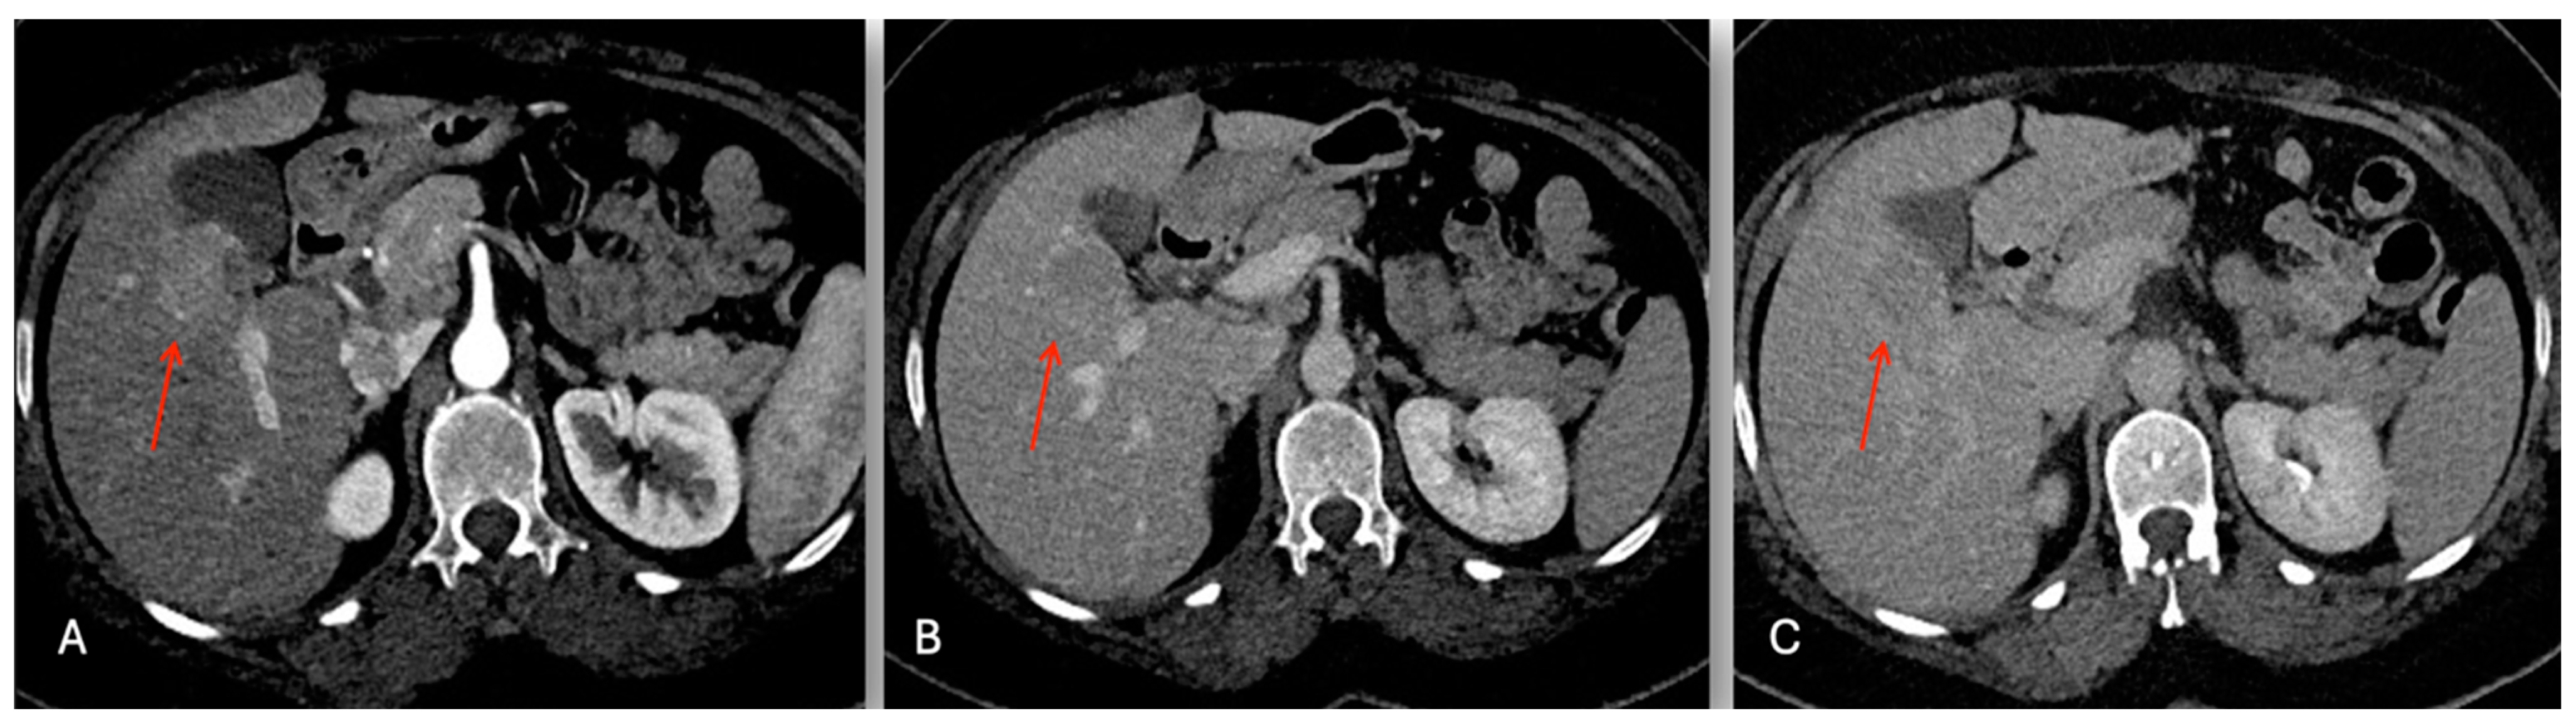

The abdominal ultrasound showed a 36 × 28 mm hypoechoic lesion in S5 near to a normal gallbladder. The Gd-EOB-DTPA-enhanced magnetic resonance imaging (MRI) showed a 38 mm tumor in segment 5 with a low intensity on the T1-weighted images, and a light high intensity on the T2-weighted images and DWI (Figure 4). The abdominal enhanced CT scan (Figure 5) confirmed a nodule with enhancement in the arterial phase and washing out in the portal, which is highly suspect for mass forming cholangiocarcinoma versus fibro-lamellar HCC within a normal liver.

Figure 5.

Contrast enhancement CT images. Liver mass in S5 (red arrow): (A) faint hyperdensity in arterial phase; progressive contrast enhancement wash-out in the portal (B); and delayed (C) phase.